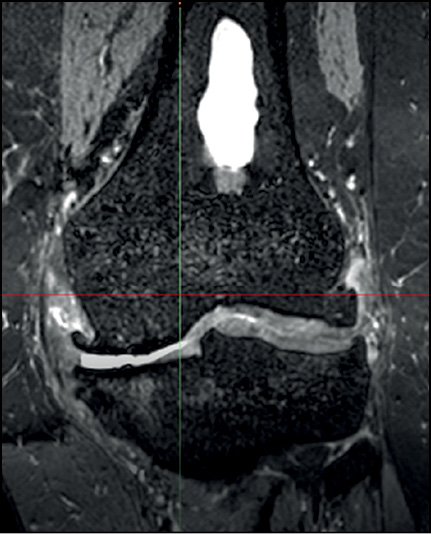

При анализе КТ и МРТ выявлены следующие особенности:

- смещение большеберцовой кости кпереди;

- суставная щель значительно сужена, преимущественно в медиальном отделе;

- медиальный и латеральный бугорки межмыщелкового возвышения деформированы, с краевыми костными разрастаниями;

- в периферических отделах суставных поверхностей большеберцовой кости определяются грубые краевые разрастания;

- в структуре дистального метадиафиза бедренной кости выявляется участок неравномерного остеосклероза (обызвествление инфаркта костного мозга) (рис. 1);

- надколенник и передняя поверхность дистального эпифиза бедренной кости с грубыми краевыми разрастаниями;

- сужение суставной щели пателлофеморального сустава.

Рис. 1. Данные магнитно-резонансной томографии больной T.

Fig. 1. Magnetic Resonance Imaging data of patient T.